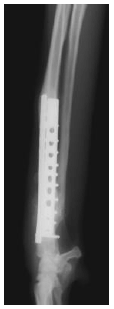

1. ボルゾイの前足の骨折(橈尺骨骨折)

プレートという器具を使って骨を固定したところです。 骨の折れ方のパターンや、大型犬であることを考慮して、 プレートを2枚使用して治療しています。 |